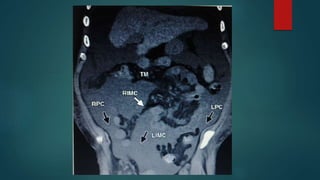

Inframesocolic spaces

below the transverse mesocolon and

transverse colon as far as the true pelvis.

 divided in two unequal spaces

RIC/LIC by the root of the mesentery

of the small intestine.

 It contains the right and left paracolic

gutters lateral to the ascending and

descending colon.

Inframesocolic spaces below thetransverse mesocolon and transverse colon as far as the true pelvis.  divided in two unequal spaces RIC/LIC by the root of the mesentery of the small intestine.  It contains the right and left paracolic gutters lateral to the ascending and descending colon.